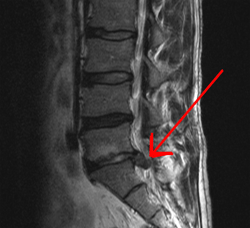

영상 검사적색 경고 징후(Red flags)가 있거나, 신경학적 증상이 호전되지 않고 지속되거나, 통증이 계속되거나 악화되는 경우에는 영상 검사가 필요하다.[3] 특히 암, 감염, 또는 마미 증후군과 같은 심각한 상태가 의심될 때는 조기에 MRI나 CT 검사를 시행하는 것이 권장된다.[3] MRI는 추간판 질환을 식별하는 데 CT보다 약간 더 우수하며, 두 검사 모두 척추관 협착증 진단에는 비슷한 유용성을 보인다.[3]

특이적 요통은 특정 질환이 원인이 되어 발생하는 요통을 의미하며, 각 질환별로 특수한 치료가 필요하다. 예를 들어, 요추의 압박 골절의 경우, 골절 부위를 일정 기간 고정하고 진통제를 투여하며, 기저 질환인 골다공증을 치료해야 할 수 있다. 경우에 따라 수술이 필요할 수도 있다.일반적으로 병력 청취와 신체 진찰을 통해 특이적 질환의 가능성을 어느 정도 배제할 수 있다. 따라서 MRI나 CT 같은 영상 진단은 만성화되었거나 치료에 잘 반응하지 않는 경우, 또는 아래에 언급될 레드 플래그 증상이 있는 경우에 고려하는 것이 보통이다.[168] 영상 진단은 암, 감염, 마미 증후군 등이 의심될 때 조기에 시행하는 것이 권장된다.[168] 추간판 탈출증 진단에는 CT보다 MRI가 약간 더 유용하며, 척추관 협착증 진단에는 두 검사 모두 유용하다.[168] 하지 직거상 검사는 추간판 탈출증 진단에 도움이 될 수 있다.[168] 지속적인 심한 요통의 원인이 되는 추간판을 특정하기 위해 추간판 조영술이 사용될 수 있으며,[175] 신경 차단술과 같은 치료적 기법이 통증 부위 파악에 도움을 줄 수도 있다.[168]